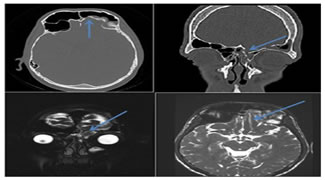

- Growing Skull Fracture

- Most growing skull fractures (GSFs) are located in the calvarium, but rare sites are the basiocciput and the orbital roof9.

- The lesion arises from a skull fracture with an associated dural tear and repeated pulsations of CSF. Eventually, the calvarial margin adjacent to fracture expands9,10.

- We can also use the term "leptomeningeal cyst/ cranio-cerebral erosion” for this condition9.

- Csf Leakage And Herniation

Figure 15: 18 year old male with history of CSF rhinorrhea, frontal neuroparenchymal herniation into the frontal sinus through the post-traumatic defect in the frontal bone.